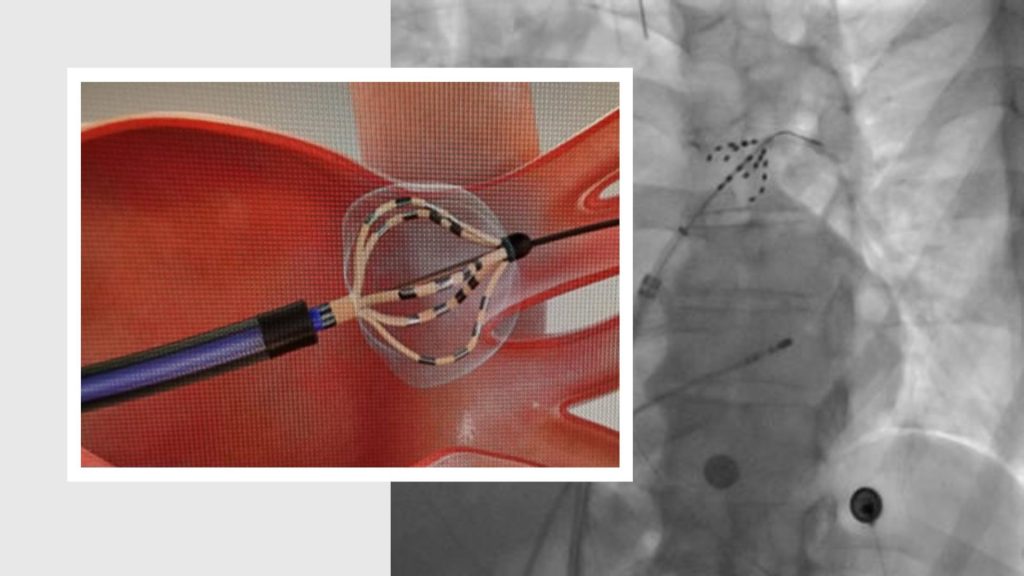

La ablación por campo pulsado se realiza mediante un cateterismo realizado por un equipo especializado en arritmias cardíacas.

La ablación por campo pulsado (Pulsed Field Ablation o PFA), nos explica el Doctor Andres Martellotto, médico de la Unidad de Arritmias, es una técnica que utiliza pulsos eléctricos ultracortos para tratar las zonas del corazón responsables de la arritmia. A través de un catéter introducido por la vena femoral, se accede a la aurícula izquierda y se aíslan eléctricamente las venas pulmonares, comúnmente involucradas en el origen de la fibrilación auricular.

Este procedimiento se diferencia de las técnicas tradicionales -como la radiofrecuencia o la crioablación- porque no utiliza calor ni frío, sino energía eléctrica altamente selectiva, que actúa únicamente sobre las células diana sin dañar los tejidos circundantes. Eso se traduce en mayor seguridad, menor riesgo de complicaciones y una recuperación más rápida para nuestros pacientes”, remarcó el Doctor Martelotto.